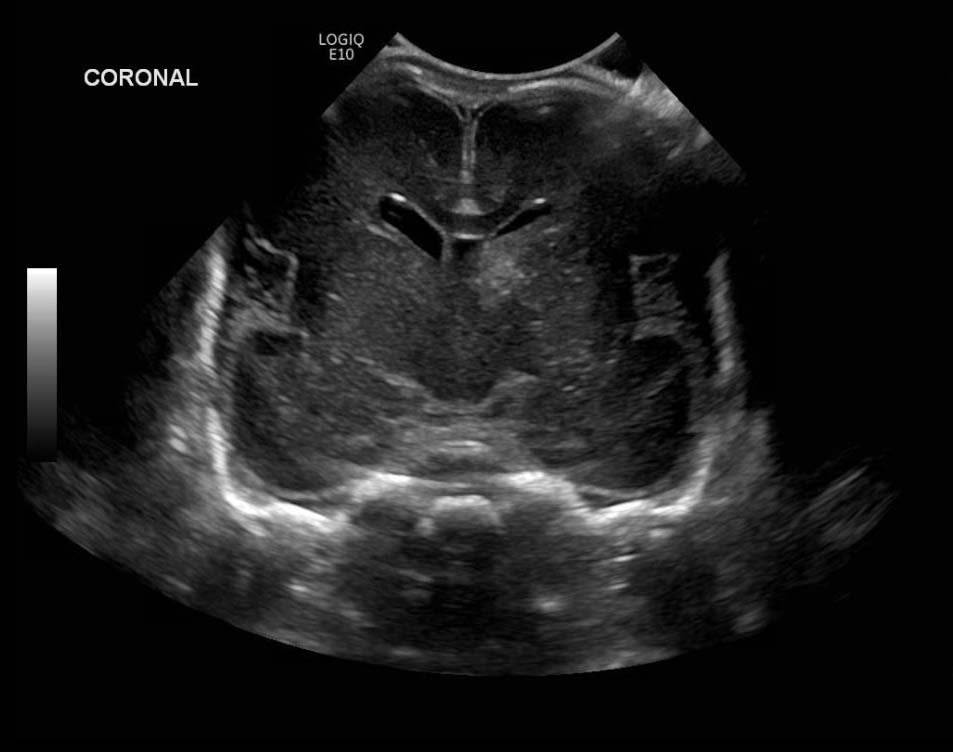

Age: 4 days (born at 24 weeks)

Sex: Male

Indication: Evaluate for germinal matrix hemorrhage

Grade 2 germinal matrix hemorrhage

Sample ReportLeft germinal matrix hemorrhage involving the caudothalamic groove and layering in the occipital horn of the left lateral ventricle without hydrocephalus (grade 2).

No abnormal brain parenchymal echogenicity or extra-axial collections.

Premature sulcation pattern.